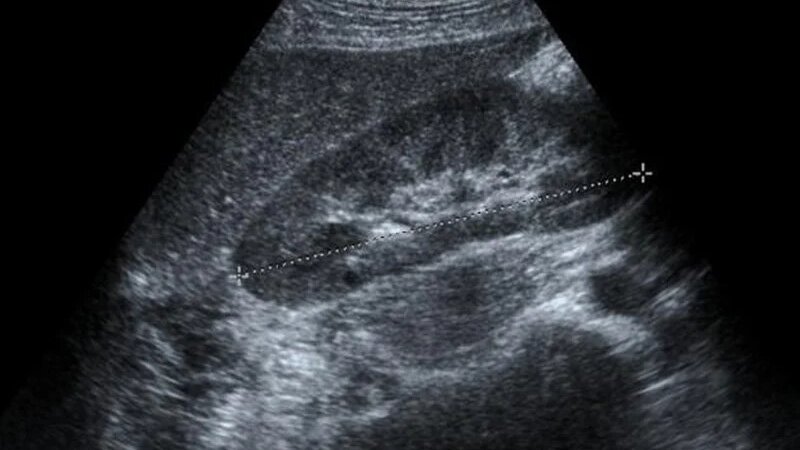

Siêu âm gan là kỹ thuật chẩn đoán hình ảnh hiện đại, cho phép quan sát rõ những cấu trúc của gan như thuỳ gan, phân thùy, hạ phân thuỳ gan cũng như hệ thống cấu trúc mạch máu của gan như động mạch chủ gan, tĩnh mạch chủ dưới gan, tĩnh mạch cửa gan và tĩnh mạch trên gan.

Kích thước gan cụ thể của mỗi người sẽ có sự khác nhau tùy thuộc vào độ tuổi, giới tính, tình trạng sức khỏe… Kích thước gan trên siêu âm được ước lượng chủ yếu thông qua ba thông số, đó là chiều dài, độ dày và chiều rộng của gan.

Theo kết quả từ nhiều nghiên cứu, trung bình kích thước gan bình thường trên siêu âm có chiều dài giao động từ 25 - 28 cm, chiều rộng trước sau khoảng từ 16 - 20 cm và độ dày khoảng 6 - 8 cm. Đây là kết quả ở những người có sức khoẻ bình thường, tuy nhiên nếu có bất thường về gan thì kích thước này cũng sẽ có sự thay đổi đáng kể.